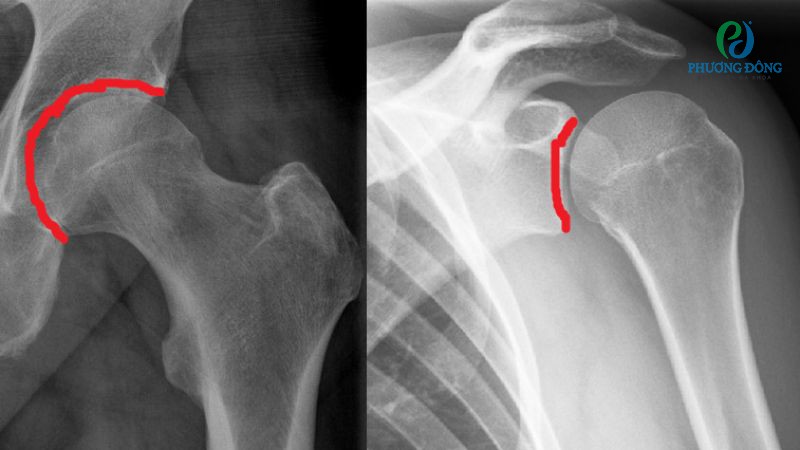

Khi đến bệnh viện thăm khám, trước tiên bác sĩ sẽ kiểm tra tổng quát tình trạng mô mềm, khớp và xương vai. Tiếp đến kiểm tra mức độ đau, khả năng cử động theo hai hình thức chủ động tự di chuyển vai và thụ động với lực từ bên ngoài.

Dựa trên kết quả khám lâm sàng, người bệnh có thể được chỉ định thêm các xét nghiệm hình ảnh nhằm loại trừ các bệnh lý gây đau và cứng vai. Cụ thể:

- Chụp X-quang giúp quan sát toàn bộ vùng xương khớp ở vi.

- Siêu âm, chụp MRI cung cấp hình ảnh tại mô mềm, hỗ trợ xác định các vấn đề khác như rách gân cơ chóp xoay vai hoặc viêm khớp.